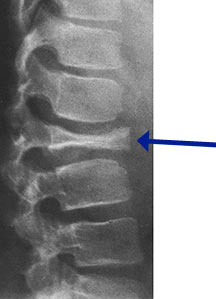

Radiographic Presentation

- Vertebral plana is braced and observed